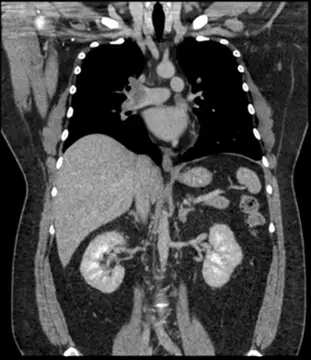

胸部 X 光 (Image 1 - CXR):

- 表現:雙側肺野透亮度尚可,但右下肺野似乎有模糊的斑塊狀陰影 (可能代表肺栓塞引起的肺梗塞或浸潤,即 Hampton's hump,但 X 光對 PE 診斷通常較不特異)。心臟輪廓可能有輕度擴大,這可能與肥胖或右心擴大有關。

- 意義:X 光在 PE 中常為正常或僅見非特異性變化,其主要價值在於排除氣胸或嚴重肺炎等其他鑑別診斷。